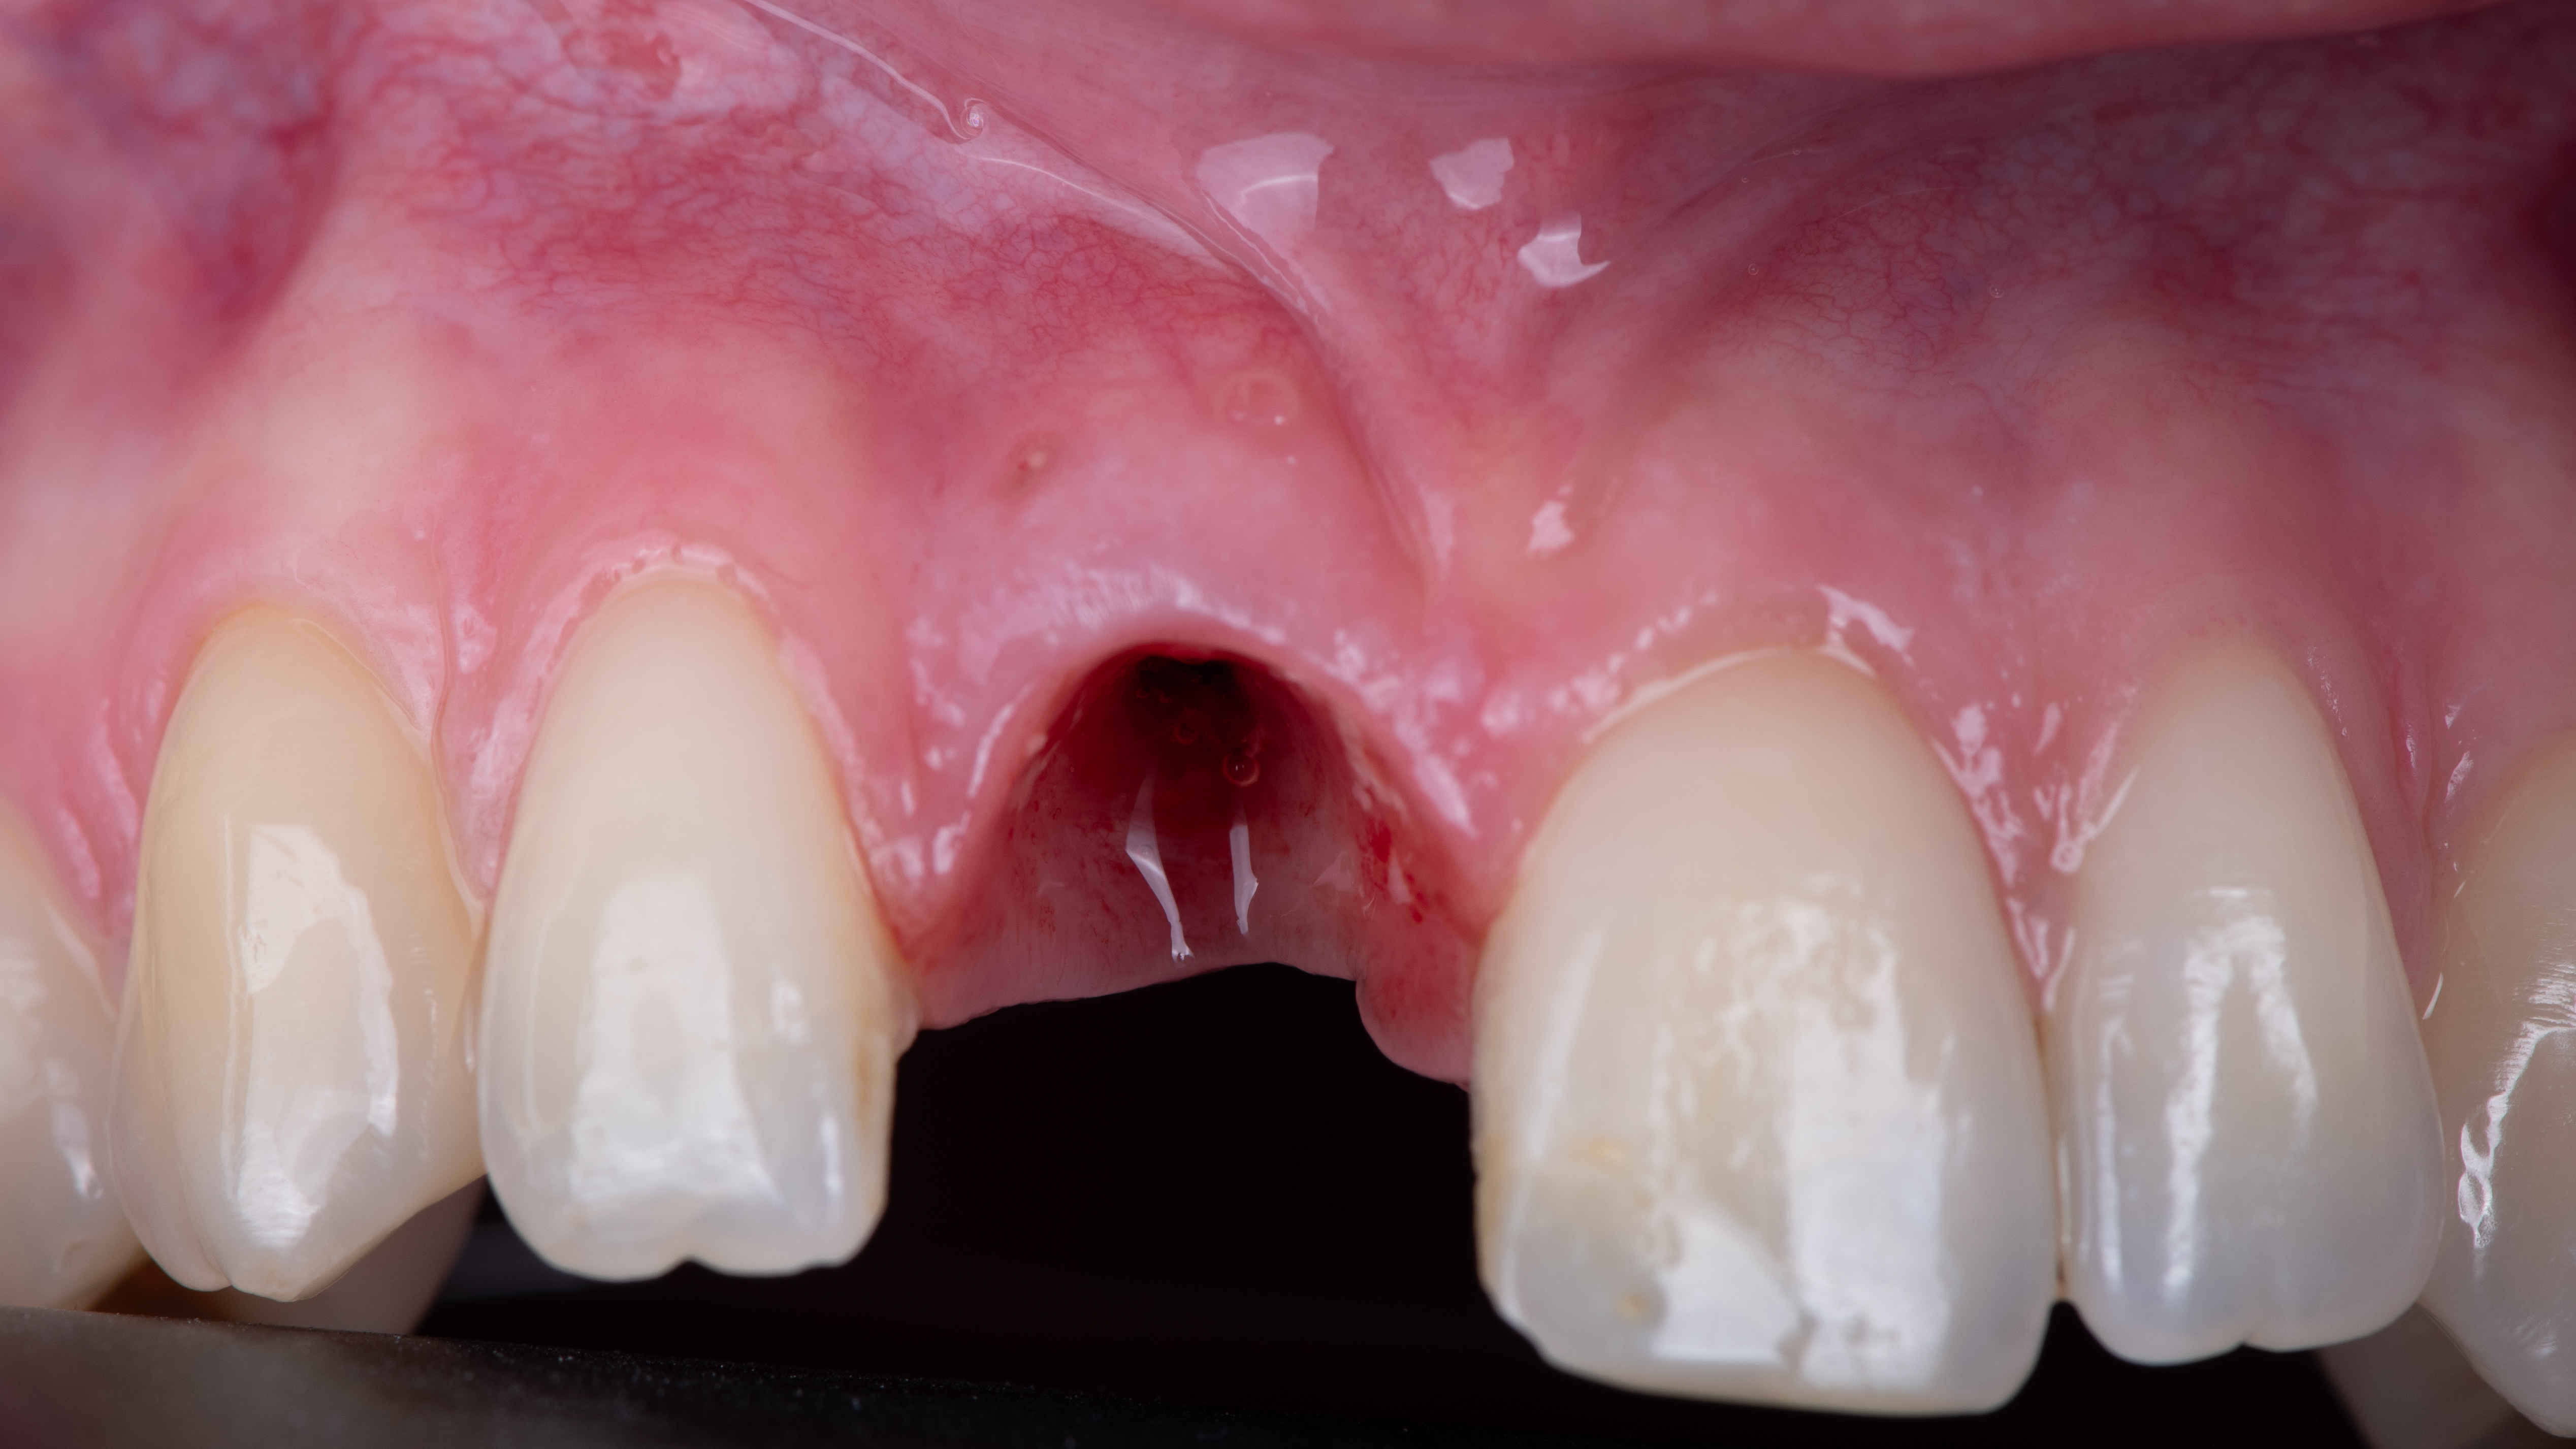

La couronne provisoire est ensuite repositionnée et les contacts en occlusions statique et dynamique sont supprimés pour éviter d’appliquer des forces sur l’implant pendant toute la période d’ostéointégration (Photo 15).